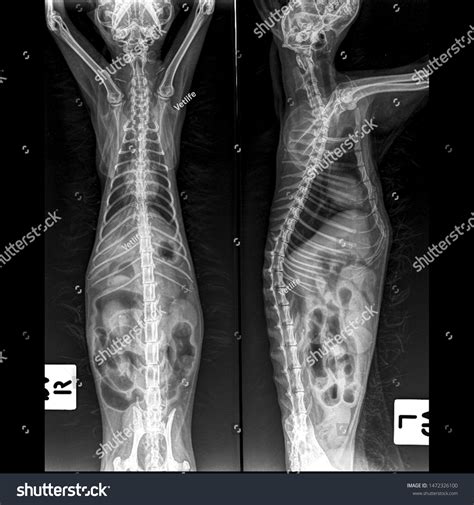

• Radiographs (X-rays): Chest X-rays can reveal inflammation, fluid, or other abnormalities in the lungs.